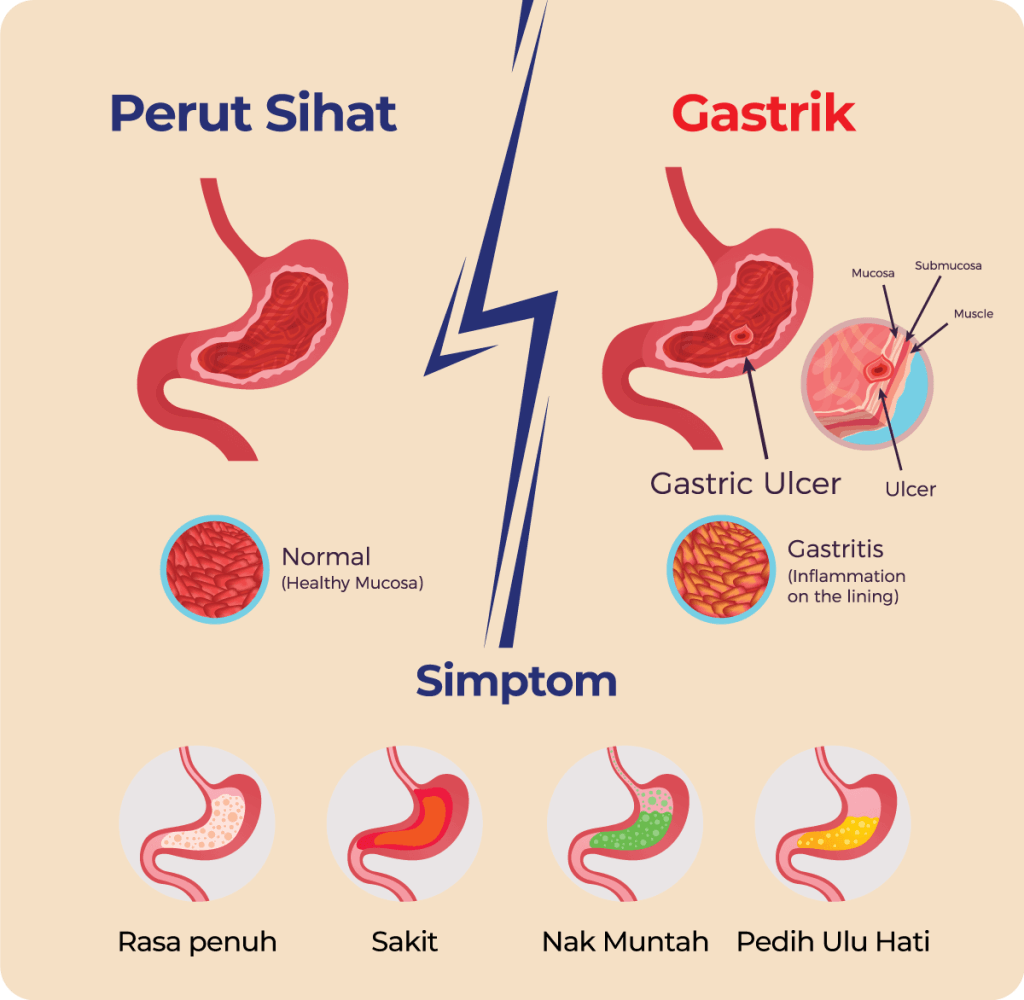

Lapisan pelindung perut yang menipis menyebabkan keradangan pada dinding perut akibat tindakblasa dengan asid perut.

Ini ialah dinding perut menipis dan membengkak akibat lapisan pelindung menipis dan tidak dapat melindungi dari asid perut.

ini gambaran perut yang sihat dengan perut yang tidak normal

Barli beta glucan dalam Ajwa Talbinah mempunyai kandungan beta glucan, iaitu sejenis serat larut yang membantu memulihkan kesihatan perut & usus.

Lapisan pelindung perut yang sihat akan melindungi perut dari terkena asid perut yang kuat

Nota : asid perut diperlukan untuk penghadaman dan bunuh kuman dalam perut. Asid perut bukan masalah, tapi lapisan pelindung perut yang menipis itu masalah sebenar.